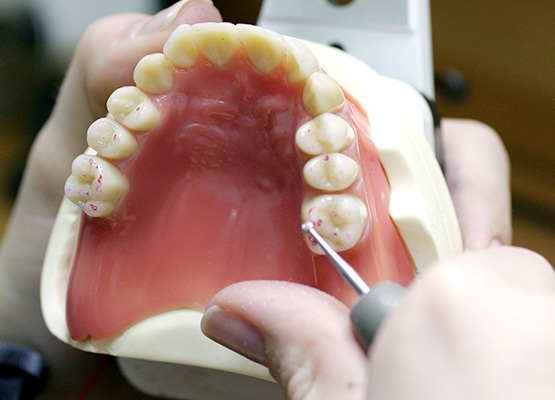

Trios3(POD)

Trios3(CART)

Oral Scanner